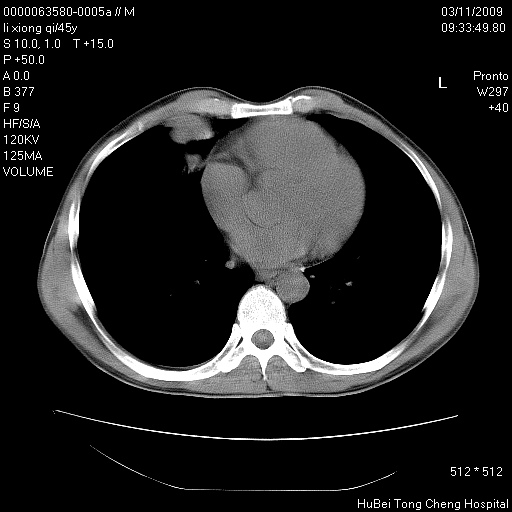

患者 男,45岁。胸痛,咳嗽伴痰中带血1月余。

临床诊断:肺结核?

胸部ct轴位平扫(层厚10mm,螺距1.5,重建间隔10mm),图像如下:

考虑肝癌肺转移